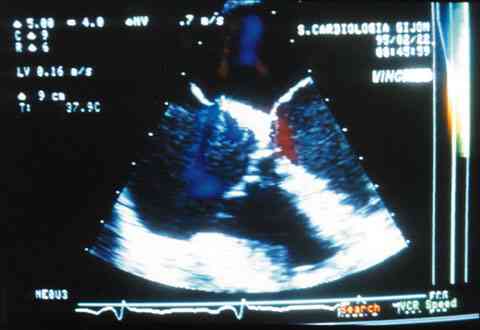

Figura 4

ECOCARDIOGRAMA TRANSESOFÁGICO PREVIA INTRODUCCIÓN DE CONTRASTE, EN EL QUE SE PUEDE APRECIAR EL TRÁNSITO INTERCAVITARIO CON LA MEZCLA DE TONOS.